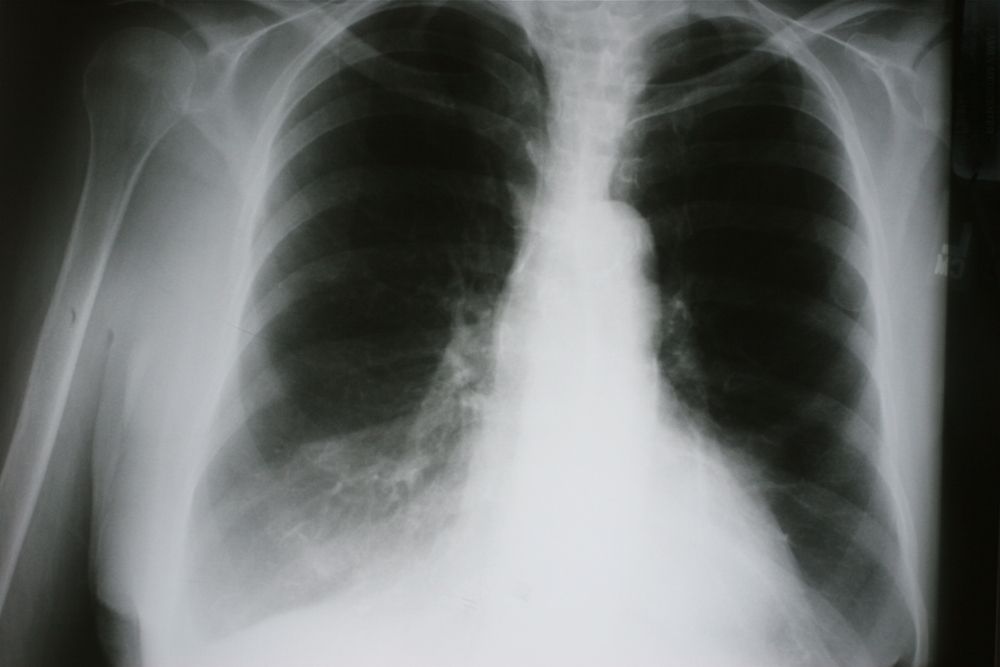

interstitial lung ct rheumatoid scan disease arthritis opacities figure bilateral untreated associated unfortunate complication shows case cureus